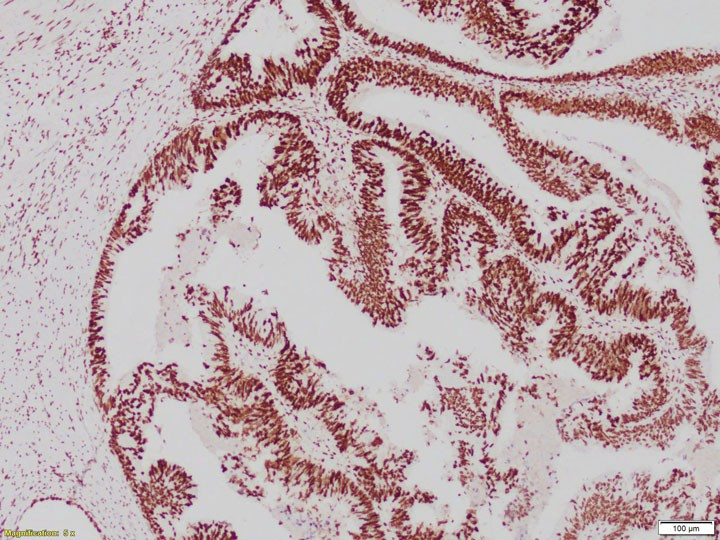

ung-thu-an.jpg

Hóa mô miễn dịch phát hiện nguồn gốc khối u - Ảnh BVCC